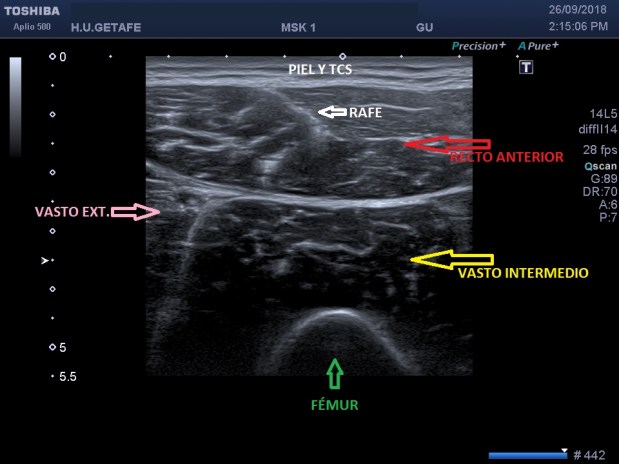

La imagen ecográfica es esta en un corte central, anterior del muslo.

Después nos movemos a ambos lados, lado interno, para Vasto interno y lado externo para Vasto externo.

En esta imagen encontramos el Rafe, línea hiperecogénica central del Recto Anterior que marcará cuanto más proximal estemos el tendón de este músculo que inserta en la cadera…Podemos usarlo de referencia anatómica.

Entre los músculo encontramos líneas hiperecogénicas de separación como las fascias.